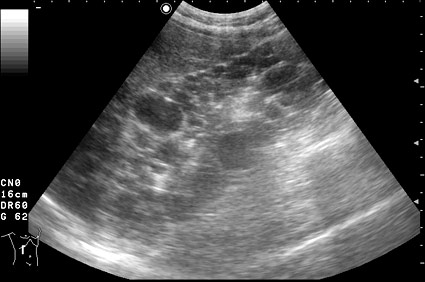

Тот же случай, сонограмма левой почки.

Ультразвуковая диагностика АДПКБ почек чаще всего не вызывает трудностей: почки значительно увеличены в размерах, определяется множество кист, от маленьких до нескольких сантиметров в диаметре. Кисты выглядят анэхогенными, при наличии примеси кровянистых и гнойных масс содержимое кист становится акустически непрозрачным, мутным. Полостная система почки дифференцируется плохо, обнаружение конкрементов чаще всего затруднено.